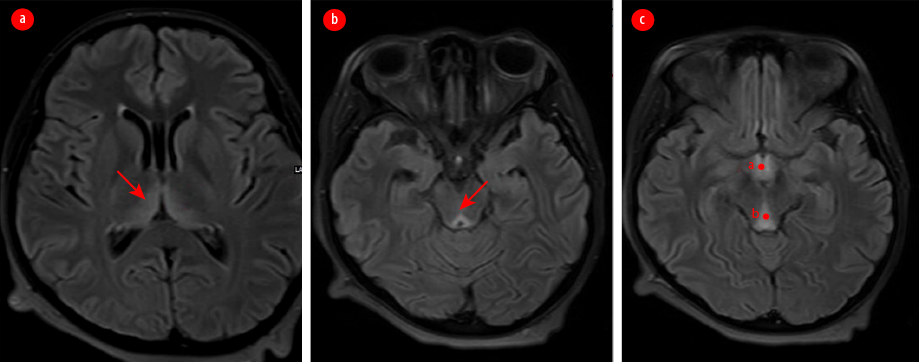

A 24-year-old primigravida at 12 weeks of gestation presented to the emergency room with weakness, mental confusion, and visual disturbance. On examination, her pulse was 100 beats per minute and blood pressure 100/60 mm Hg. She appeared disoriented and had nystagmus, photoreactive pupils, and preserved visual acuity. She had an atypical gait with a history of occasional falls. She revealed that she experienced excessive nausea and vomiting since her conception and had been hospitalized thrice to manage episodes of hyperemesis gravidarum. Blood investigations revealed hemoglobin = 11 gm/dL, potassium = 2.8 mmol, sodium = 133 mmol, blood glucose = 60 mg/dL, and normal renal, liver, and thyroid functions. Urine analysis showed ketonuria. Electrocardiogram revealed sinus tachycardia while ultrasound showed a single live intrauterine fetus of 12 weeks of gestation. Magnetic resonance imaging (MRI) of the brain reported bilateral symmetrical altered signal intensities in the medial and posterior aspects of both thalami, periaqueductal grey matter, and tectal plate, suggesting WE [Figure 1].

Figure 1: MRI of the brain showing symmetrically altered intensities of signals in the (a) medial and posterior aspects of both thalami, (b) periaqueductal grey matter, and (c) tectal plate.

If the correction of fluid imbalance in HG is done with dextrose without thiamine supplementation, WE can be precipitated. A recent systematic review of WE in pregnancy revealed a maternal mortality rate of 5%, and fetal mortality rate of 50% despite diagnosis and treatment.5 WE has also been associated with permanent neurologic damage and Korsakoff syndrome. Korsakoff syndrome is characterized by marked irreversible deficiency of antegrade and retrograde memory and can be fatal in 10–20% of cases.9 The fetal complications associated with WE are miscarriage, preterm birth, intrauterine growth retardation, and intrauterine fetal death in case of severe maternal compromise.9 The typical findings in MRI are symmetrical hyperdense lesions in the thalamus, mammillary bodies, tectal plate, and periaqueductal area.13 The diagnosis of WE is based on the clinical findings and rapid reversal of symptoms with thiamine.